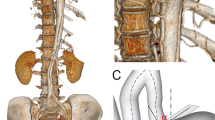

Figure 1 shows the geometric models reconstructed from the first set of post-surgery CTA images for all 17 patients. A transparent view for each model is also provided, which allows visualization of the location and shape of the tears. The location of the proximal entry tear is highlighted by a red circle in the transparent view. Among the 17 cases, only one patient (S1#2) had a fully thrombosed FL on follow up scan, while the others had a patent FL starting from the distal ascending aorta or the distal arch at the level of the left subclavian artery (LSCA). Three patients in the stable group had a short FL that merged with TL at the distal arch in one patient (S1#1), and in the mid-thoracic aorta of the other two (S1#4 and S1#5). A summary of key geometric parameters can be found in Table 1. In addition, statistical analyses of the evaluated parameters were performed using the non-parametric Mann–Whitney U test and a p-value < 0.05 was defined statistically significant. All results are presented as median [25 percentile, 75 percentiles] as summarised in Table 2.

CTA data were obtained with a multi-slice computed tomography scanner (Somatom Definition Flash, Siemens Medical Solutions, Germany). The quality of CT images was sufficient to include all the important geometric features, with slice thickness and increment ranging from 0.63–1 mm and 0.5–0.8 mm, respectively. All patient-specific geometries were reconstructed from the first set of CTA data using a semi-automatic threshold-based segmentation tool (Mimics 20.0, Materialise HQ, Leuven, Belgium). As shown in Fig. 5a, several essential anatomical features can be recognised clearly from the CT images, including the dissection tears, intimal flap, and the true and false lumen. The regions of interest had to be manually segmented based on the local greyscale intensity (Fig. 5b). The segmented 2D masks were then integrated to generate a 3D fluid domain, which was smoothed to eliminate any reconstruction errors. 3-D surface smoothing was performed by using a cubic spline algorithm. For every patient, the computed region was created from the aortic sinotubular to the level of diaphragm. Three main arch branches were also included in the reconstructions (Fig. 5c). Since post-surgical dilatations mainly occurred in the thoracic aorta, the abdominal aorta was excluded from the analysis to reduce the computational time.

Workflow of patient-specific geometry reconstruction from computed tomography (CT) scans to mesh generation. (a) Target lumen areas are identified on CT, (b) cross-sectional slices were manually segmented to separate the true and false lumen, (c) dissection geometry is defined as the fluid domain of interest. All aortic geometries were smoothed and cut out from the sinotubular junction to the level of diaphragm, including the arch vessels. (d) Meshing, where the fluid domain was discretised into a large number of numerical grids with local mesh refinement performed, and (e) hybrid unstructured mesh comprising of a tetrahedral core and prismatic wall layers.

After geometry reconstruction, a number of morphological measurements were taken using Mimics software including distances, best-fit diameters, and volumes, as summarised in Table 1. It should be mentioned that tortuosity was defined as a ratio between the distance along the centreline and the linear distance, which was calculated for the entire aorta, and for the ascending and descending aortas separately. The re-entry tears were identified on the CTA images as openings in the dissection membrane that were located distal to the primary entry tear. It should be noted that the ‘primary entry tear’ referred to in this paper is the most proximal tear in the residual dissected aorta since the initial primary tear in the ascending aorta has been resected during surgery.